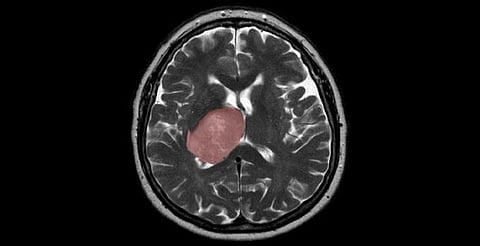

If you eat undercooked meat then you may need to stop it, as researchers have found a link between Toxoplasma gondii (T. gondii) infection and the risk of glioma, a rare type of brain cancer, in adults.

T. gondii is a common parasite that is most commonly acquired from undercooked meat and may lead to the formation of cysts in the brain.

These results suggest that reducing exposure to this common food-borne pathogen could provide a modifiable risk factor for highly aggressive brain tumors in adults.

Although glioma is a relatively rare disease, it is a highly fatal cancer. Globally in 2018, there were an estimated 300,000 incident cases and 241,000 deaths due to brain and other nervous system cancers, the researchers said.

The majority (80 percent) of malignant brain tumors are gliomas, for which the estimated five-year relative survival rate is a stark 5 percent, they added.